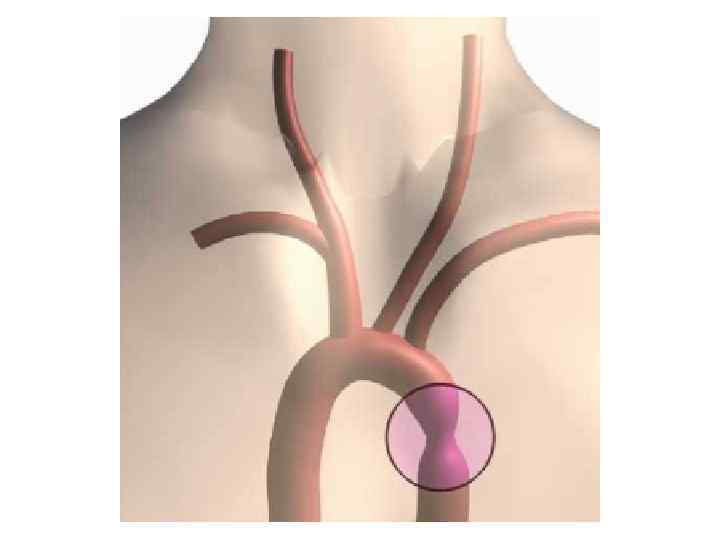

КОАРКТАЦИЯ АОРТЫ 1. В ОСНОВНОМ ГОЛОВНАЯ БОЛЬ ПЕДИАТРОВ 2. ТЕРАПЕВТЫ ВИДЯТ ОПЕРАТИВНО КОРРЕКТИРОВАННЫХ БОЛЬНЫХ 3. АГ ЛЕЧИТСЯ КАК ГБ, НО НАДО ПОМНИТЬ О ЧАСТОМ АТЕРОСКЛЕРОЗЕ (СИСТОЛИЧЕСКАЯ АГ) И ГИПОПЛАЗИИ ПОЧЕК (НЕФРОГЕННАЯ АГ)

КОАРКТАЦИЯ АОРТЫ 1. В ОСНОВНОМ ГОЛОВНАЯ БОЛЬ ПЕДИАТРОВ 2. ТЕРАПЕВТЫ ВИДЯТ ОПЕРАТИВНО КОРРЕКТИРОВАННЫХ БОЛЬНЫХ 3. АГ ЛЕЧИТСЯ КАК ГБ, НО НАДО ПОМНИТЬ О ЧАСТОМ АТЕРОСКЛЕРОЗЕ (СИСТОЛИЧЕСКАЯ АГ) И ГИПОПЛАЗИИ ПОЧЕК (НЕФРОГЕННАЯ АГ)